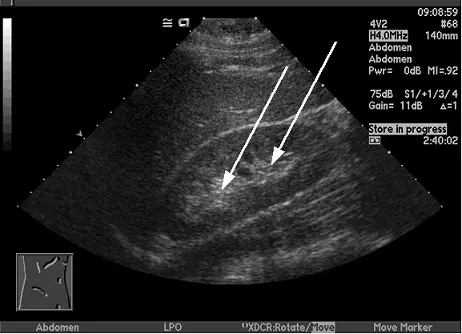

附圖中箭號所指高回音的部位最可能為何?

影像為一幅典型的腹部超音波掃描,呈現腎臟的長軸切面(longitudinal view)。

- 腎臟中央:影像中兩根白色箭號精確指向腎臟正中央、呈現明顯「高回音」(hyperechoic / bright echogenicity)的區域。此中心區域的高回音特性,主要來自於該處富含的脂肪組織、血管、淋巴管以及集尿系統等多重構造交界面所造成的強烈音波反射。

- (B) 腎竇部(renal sinus):位於腎臟最中央,內部包含腎盞、腎盂、血管、神經及大量的腎竇脂肪(renal sinus fat)。由於脂肪組織以及複雜的結構交界面會產生強烈的超音波反射,使其在影像上呈現極具特徵的「高回音(hyperechoic)」。影像中箭號直指該中心高回音區,故此為正確選項。

根據影像解剖學的特徵,兩根箭號所指之處為腎臟正中央最亮的區域。在腹部超音波中,腎臟由外而內的回音表現有明顯層次:最外層的腎皮質為中低回音,內層的腎髓質為更低的低回音,而最中心的腎竇部(renal sinus)因為富含脂肪與纖維組織,呈現強烈的高回音。綜合上述影像特徵與組織聲學特性,該部位最可能為腎竇部,故正確答案為 (B)。